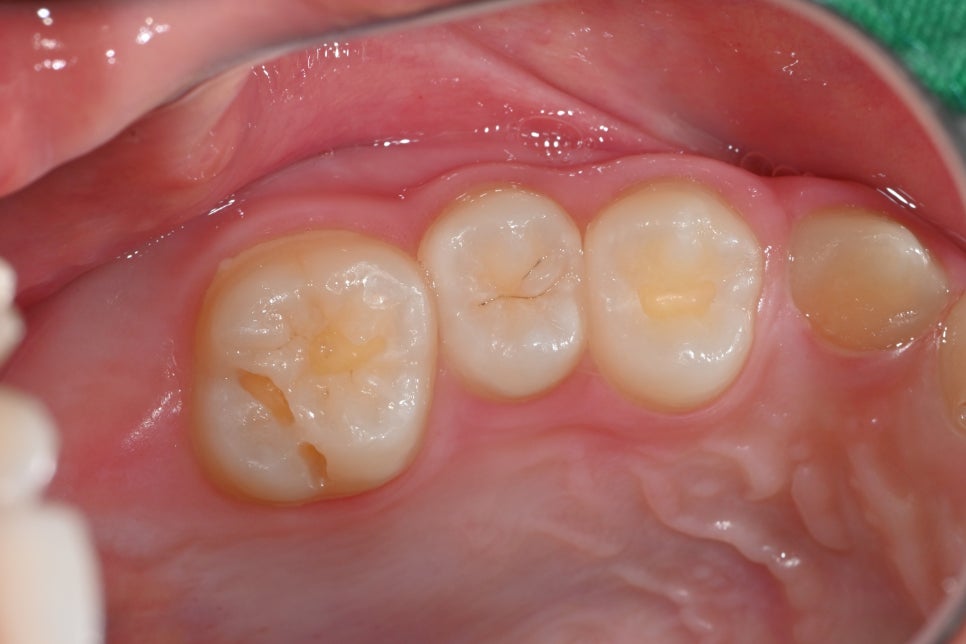

🛠 치료 중 사진

충치 부위를 정리하고 레진 수복을 준비하는 과정입니다.